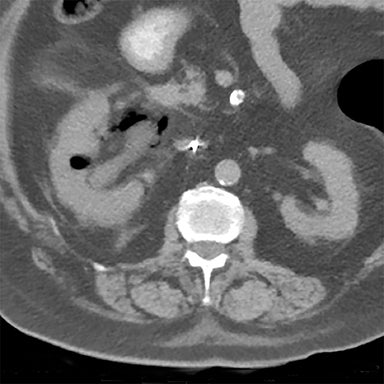

Emphysematous pyelonephritis (EPN) is a severe gas forming infection of renal parenchyma most commonly affecting Diabetic patients. It is a life-threatening, emergency condition caused by glucose-fermenting bacteria, typically E. coli, which results in rapid kidney destruction. Common symptoms include fever, abdominal pain, and septic shock

a severe, necrotizing, gas-forming infection of the renal parenchyma, most commonly affecting diabetic patients. It is a life-threatening, emergency condition caused by glucose-fermenting bacteria, typically E. coli, which results in rapid kidney destruction. Common symptoms include fever, abdominal pain, and septic shock.

Diagnosis: CT scanning is the preferred imaging modality to confirm the diagnosis, which shows gas within the renal parenchyma, collecting system, or surrounding tissues.

Classification: EPN is typically classified by severity (Class 1–4) based on the extent of gas spread on CT, ranging from confined to the parenchyma to extending beyond the renal fascia.